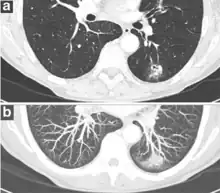

FDG-PET study of a 71-year-old woman with a solitary pulmonary nodule (thin arrow) in the left lower lobe near the heart. The scan also revealed abnormal increased activity at the gastro-esophageal junction (thick arrow). The final diagnosis was non-Hodgkin lymphoma at both sites.

If there is an intermediate risk of malignancy, further imaging with positron emission tomography (PET scan) is appropriate (if available). It can be done simultaneously as a CT scan in the form of PET-CT. Around 95% of patients with a malignant nodule will have an abnormal PET scan, while around 78% of patients with a benign nodule will look normal on PET (this is the test sensitivity and specificity).[15] Thus, an abnormal PET scan will reliably pick up cancer, but several other types of nodules (inflammatory or infectious, for example) will also show up on a PET scan. If the nodule has a diameter of less than one centimeter, PET scans are often avoided because of an increased risk of falsely normal results.[15][16][17] Cancerous lesions usually have a high metabolism on PET, as demonstrated by their high uptake of FDG (a radioactive sugar).